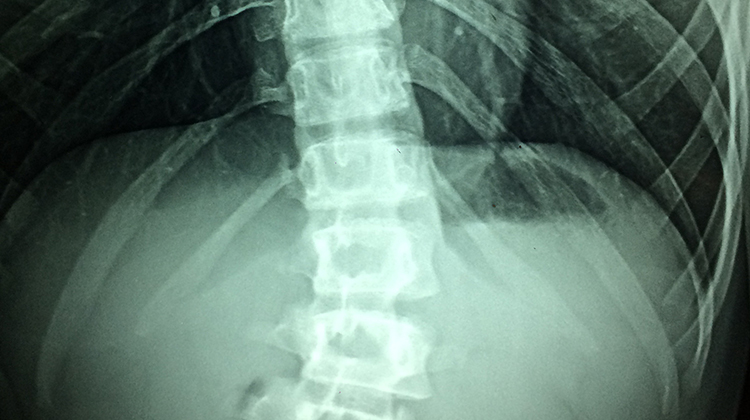

허리디스크 질환설명

허리디스크는 요추(허리)의 뼈와 뼈 사이의 추간판이 탈출하거나 파열되어 요추(허리) 신경이 압박을 받아 허리에 통증이 일어나는 질환입니다.

‘디스크(추간판)’는 원래 척추의 뼈와 뼈 사이에 있는 편평한 판 모양의 물렁뼈를 가리키는 말입니다.

디스크의 외부는 섬유륜이라는 막으로, 내부는 젤라틴처럼 탄력이 있고 점성을 띠는 반액체인 수핵으로 구성되어 있습니다.

이 외부의 섬유륜이 외상이나 퇴행성 변화 등에 의해 찢어지거나 파열되면 내부의 수핵이 밖으로 밀려 나와 주위 조직, 특히 척추 신경을 압박하면서 통증 등의 증상을 유발합니다. 이것을 ‘디스크’, 또는 ‘추간판탈출증’이라고 합니다.

각각의 척추신경은 고유한 영역의 감각과 운동을 담당하기 때문에 디스크가 발생한 위치에 따라 통증의 위치와 양상이 달라집니다.

허리디스크의 경우 제4번과 제5번 요추(허리뼈) 사이, 제5번 요추와 제1번 천추(엉치뼈) 사이에서 주로 발생하는데, 예를 들어 탈출된 디스크가 다섯 번째 요추신경을 압박하면 종아리 바깥쪽이나 발등, 발바닥 등에 통증이나 저린 감각을 느끼게 됩니다.